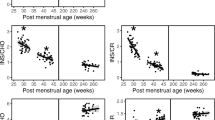

Relevant corrected ages of all 127 VPIs included in our study, with mean, median, standard deviation (SD) and range given in weeks were as follows: gestational age: 29.62, 29.86, 1.8 and 7.15; age at the time of MRI: 40.44, 40.43, 1.47 and 15.56; and age at the time of clinical testing for cognitive and motor development: 11.95, 12, 0.84 and 6.

Out of 300 VPIs who received an MRI scan at TEA, 278 could be evaluated at 12 months corrected age for their motor skills. Out of 127 included VPIs, 24 were excluded in a second step due to some missing metabolite peaks. In total, 103 complete MRS datasets of VPIs for the prediction of motor delay were available. Of those, 13 (12.6%) infants were categorised as motorically delayed at 12 months corrected age. There was no difference in the rate of neurodevelopmental delay (12.6 vs. 17.1%, p = 0.391) or the mean scores of motor scales (100 ± 16.3 vs. 97 ± 17.5, p = 0.226) between included and excluded infants.

Cognitive development prediction

Out of 300 VPIs, 276 VPIs could be evaluated regarding their cognitive development at 12 months corrected age.

Out of 127 included VPIs, 12 were excluded in the second step due to some missing metabolite peaks. In total, 115 complete datasets of VPIs for the prediction of cognitive outcome were available. Among them, seven (6.1%) VPIs were identified as having a cognitive delay at the corrected age of 12 months. The proportion of cognitively delayed VPIs was similar to the excluded group, nine of 161, 5.6% (p = 1.000). Again, there was no difference in the mean score for the cognitive scale of Bayley-III between included and excluded infants (104 ± 15.1 vs. 102 ± 16.8, p = 0.290).